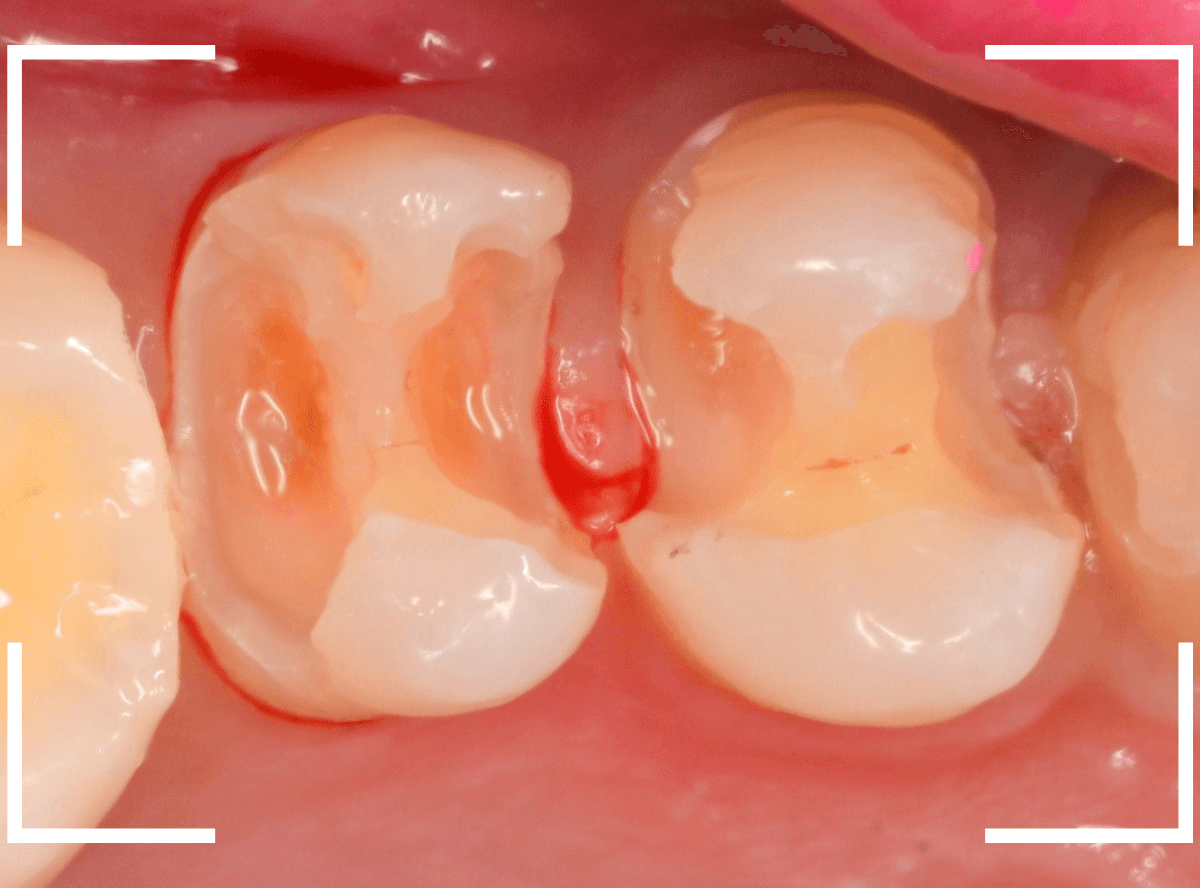

Case.15 歯肉の中まで、虫歯が進行

今回は、下の奥歯が虫歯になってしまった方です。

銀歯の下が大きくかけていますが、神経を取っている歯なので痛みはありません。

隣りの奥歯は、土台のまま治療途中になっています。

レントゲン写真で確認します。

赤い部分が虫歯、青い線が歯肉のラインです。

奥歯2本とも虫歯になっています。

どちらも虫歯が深く、歯肉の中まで入り込んでいると思われます。

この虫歯の深さは、最悪、抜歯が必要になるかもしれないケースです。

神経のない歯ですが、歯肉を処置する必要があるため、麻酔をして治療します。

まず、つめものを外します。

歯肉を処置しながら、虫歯を除去します。

虫歯の全て除去後、止血したところです。

かなり深いところまで虫歯が進行していましたが、なんとかぎりぎり抜歯せずに、土台を作って噛み合わせを回復できそうです。

神経を取った歯は、虫歯がいくら進行しても痛みにならず、最悪、抜歯一直線になってしまいます。